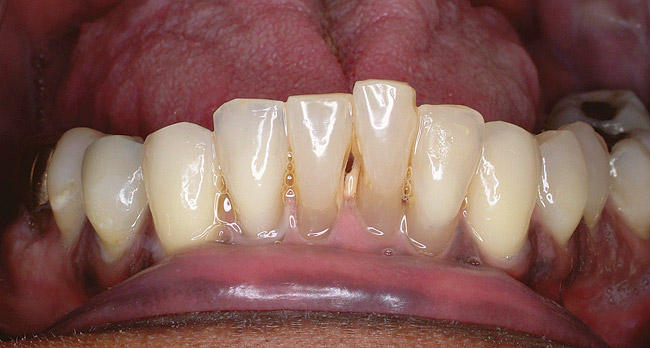

Figure 5a  Radiograph of severe periodontal bone loss on the mandibular left central incisor.

Figure 5a

Figure 5b  Facial view of the periodontally compromised central incisor.

Figure 5b

Figure 5c  Facial view after extraction of the central incisor.

Figure 5c